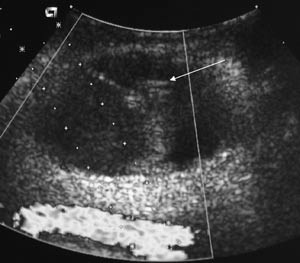

Aneurismet, aneurismehalsen og den punkterte arterien ble identifisert med ultralydundersøkelse og doppler (fig 1). Inklusjonskriteriene for behandlingen med trombin fremgår av tabell 2. Perifer puls ble sjekket før og etter behandling, eventuelt ble det utført en dopplerundersøkelse av arteriene på foten. Aneurismet ble punktert ultralydveiledet med en 20 G nål som var 15 cm lang. Målet var å plassere nålen i den sirkulerte del av aneurismet fra ventralsiden og på en slik måte at nålespissen pekte bort fra aneurismehalsen. Det ble ikke foretatt noen kompresjon. Med en 1 ml sprøyte ble trombin 1 000 IE/ml injisert (Trombostat, hetteglass med 5 000 IE). Ved pågående dopplerundersøkelse injiserte vi 0,1 ml om gangen inntil det var mulig å se at blodstrømmen i aneurismet ble opphevet (fig 2). Man satte en maks grense på 1 ml for aneurismer med bare ett lokulament, og 1,5 ml som øvre grense ved pseudoaneurismer med flere rom. Målet var å sette så lite trombin som mulig og å stoppe injeksjonen umiddelbart etter at blodstrømmen opphørte, noe som vanligvis tok få sekunder (fig 2). Undersøkelser har vist at aneurismehalsen lukkes spontant etter ca. ti minutter (3). Om man tilstreber å lukke også halsen, øker risikoen for å få trombin over i den native arterien. Etter behandlingen anbefalte vi sengeleie i to timer og pasienten kunne eventuelt utskrives samme dag. Ultralydkontroll ble utført neste dag hos de inneliggende pasientene og poliklinisk hos dem som var utskrevet. Pasientene ble ved ultralydkontrollen informert om å ta kontakt med oss, dersom de på ny skulle få symptomer fra punksjonsområdet. Det ble ikke gjort systematisk oppfølging av pasientene etter dette, da andre har vist at slik oppfølging ikke er nødvendig (3).

Punksjonskomplikasjoner etter en karintervensjon er vanlig, og består oftest av mer eller mindre uttalt subkutan blødning. Dette kan gi smerter, tyngdefornemmelse, blålig misfarging og en palpabel kul i nærheten av punksjonsstedet. De fleste hematomer resorberes etter noen dager til uker. Dersom man rutinemessig utførte ultralydundersøkelse med doppler dagen etter punksjonen, ville man finne at en del av disse hematomene var sirkulert og stod i direkte kommunikasjon med den punkterte arterien. Dette kalles et pseudoaneurisme (fig 1). Til forskjell fra et ekte aneurisme, er dette ikke omgitt av en arterievegg. Det som hindrer fri blødning, er mottrykk fra vevet omkring arterien. Et slikt ekspansivt hematom kan forårsake store skader på omliggende vev og gi opphav til alvorlige blodtap (1).